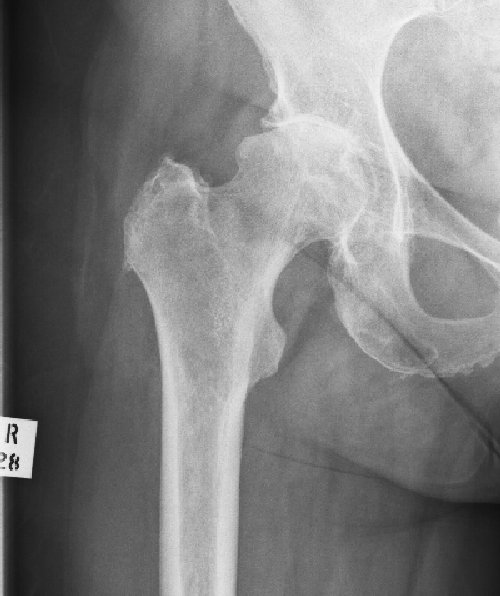

Avascular Necrosis

This is a condition caused by a failure of the blood supply to a part, or the whole, of the femoral head. As the bone is exposed to daily trauma it cannot regenerate and may start to collapse. The extent of the collapse is variable, healing will solidify the head but may lead to a mis-shapen head and therefore early osteoarthritis.

In extreme cases the whole femoral head may fragment and the bone dissolves away.

31/03/2011